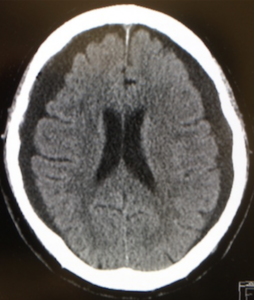

| びまん性脳腫脹 | 一次性脳損傷に加え、受傷早期の低血圧、低酸素血症、高二酸化炭素血症などによる二次性脳損傷が加わりびまん性脳腫脹が生じると考えられている。![]() |

|